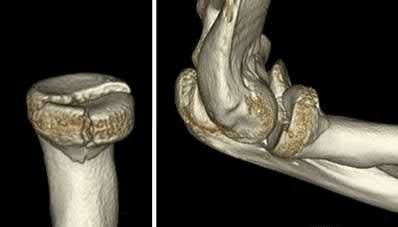

A 24-year-old woman is thrown from her motorcycle and sustains the closed injury shown in Figures A through C. Open reduction and internal fixation is planned. What surgical technique will best allow visualization of the joint surface and allow early range of motion?

Figures A and B show a AO/OTA type C2 intraarticular distal humerus fracture. Figure C is a coronal CT scan showing intraarticular comminution. Illustration A shows fixation of the fracture with bicolumnar plating through an olecranon osteotomy approach. Illustration B shows the various approaches to the distal humerus (left, Campbell triceps splitting; center left, O'Driscoll triceps reflecting anconeus pedicle; center right, Bryan-Morrey approach, leaving the triceps attached laterally to the fasciocutaneous flap, but elevating it off the ulna; right, olecranon osteotomy). Illustration C shows 3 methods of olecranon osteotomy (A and B, Intra-articular transverse; C-F, Extra-articular oblique; G, Intra-articular chevron).